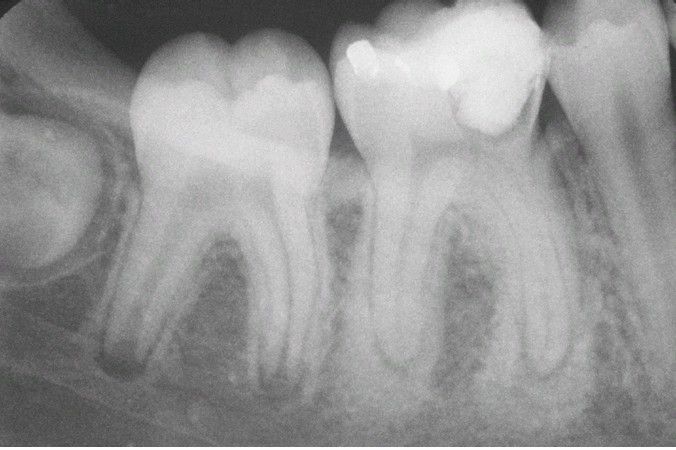

Condensing Osteitis.

Increased areas of radiodensity surrounding the apices of the nonvital mandibular first molar.